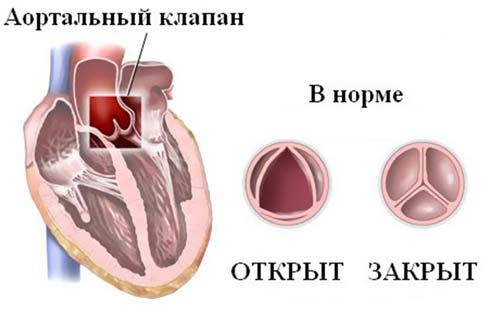

Аортальный клапан

Это анатомическое образование играет ключевую роль в прекращении связи между левым желудочком (ЛЖ) и аортой в момент расслабления сердечной мышцы (диастолы). Створки данного клапана плотно смыкаются при выбросе крови, что предотвращает её обратное движение из аорты в желудочек. В норме его площадь составляет 3-4 см².

Врожденные или приобретенные дефекты могут представлять серьезную угрозу:

- трещины;

- рубцы;

- уплотнения;

- сжатия.

Сочетание этих факторов может привести к развитию пороков сердца.

Аортальные сердечные пороки

При наличии отклонений от нормы могут развиваться аортальные пороки, такие как комбинированный порок, стеноз и недостаточность.

Стеноз

Клапанные створки срастаются, что приводит к уменьшению диаметра отверстия. Это затрудняет отток крови из желудочка.

Симптомы стеноза:

- гипертрофия левого желудочка при отсутствии артериальной гипертензии и толщине перегородки 15 мм и более;

- объем выброса крови в аорту составляет менее 50%;

- площадь отверстия сокращается до 1 см² и меньше.

Давление в области между аортой и желудочком превышает 40 единиц.

Недостаточность

Створки не могут полностью закрываться из-за повреждений, что позволяет крови из аорты возвращаться в желудочек.

Критерии недостаточности, при которых показано хирургическое вмешательство:

- объем выброса крови в аорту составляет менее 50%;

- объем обратного тока крови превышает 60 мл за одно сердечное сокращение;

- диаметр полости левого желудочка увеличен до 75 мм.